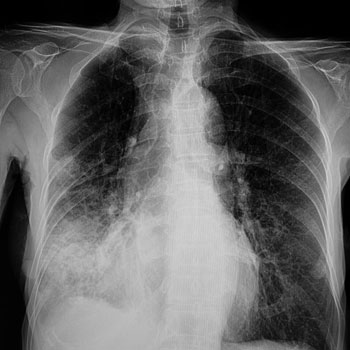

Isolating a pneumonia diagnosis can be challenging, particularly for internal medicine physicians without easy access to a chest X-ray, said Mark Ebell, MD, MS, a professor of epidemiology at the University of Georgia College of Public Health in Athens, who has studied pneumonia diagnosis and treatment, including for the recent JGIM meta-analysis. Since there's no well-validated risk score, physicians must rely upon their overall clinical impression, and signs and symptoms can be misleading, he said.

Clinical signs and symptoms alone aren't sufficient to diagnose pneumonia, according to the ATS/IDSA guideline. But in practice, physicians working in an outpatient setting may not have a chest X-ray on site, which contributes to overprescribing, Dr. Metlay said.

Some studies, including research involving Dr. Metlay, indicate that pneumonia can sometimes be largely ruled out without a chest X-ray. One systematic review and meta-analysis found that adults with an acute respiratory infection who had normal vital signs and a normal pulmonary exam were very unlikely to have CAP. Given a baseline pneumonia risk of 4%—based on other research showing that most patients with acute cough don't have pneumonia—patients with normal vital signs and a normal exam only have a 0.4% likelihood of having contracted the infection, according to the findings, published in 2019 in the Journal of the American Board of Family Medicine.

The acute bronchitis guidelines from the American College of Chest Physicians, Dr. Burke noted, provide guidance regarding whether a chest X-ray might be helpful. If the patient's vital signs are normal and the pulmonary exam doesn't identify any abnormalities, such as focal consolidation, egophony, or fremitus, the likelihood of pneumonia has been reduced "sufficiently to eliminate the need for a chest radiograph," the guidelines' authors wrote.

But when there's any uncertainty, physicians should consider ordering a chest X-ray, given the potentially life-threatening stakes involved, Dr. Burke said. "That's something to me where you go a bit of an extra step to feel confident in your diagnostics," she said. "If you think someone has CAP, I think they deserve a chest X-ray."